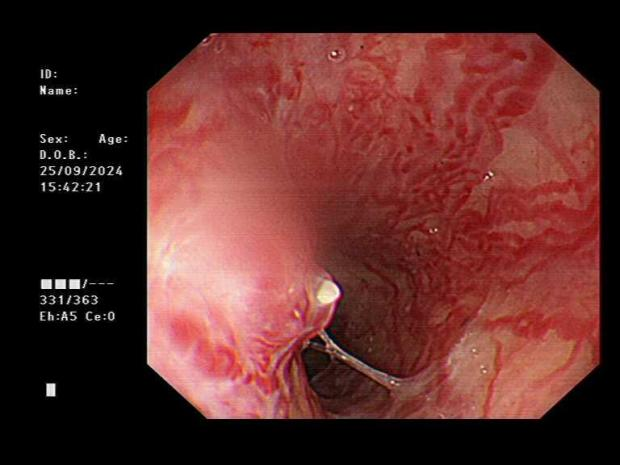

消化内科团队与患者及家属充分沟通病情后,面对高风险的情况,秉持“救死扶伤”的宗旨,顶着压力冷静沉着为患者行急诊胃镜检查。胃镜显示食管中下段可见四条静脉曲张,最大直径约1.0cm,交通支形成,红色征阳性,食管中段距门齿30cm及下段距门齿38cm各见一处白色血栓头;下段距门齿32cm偏后壁静脉曲张可见一破裂口并活动性喷射样出血。经患者家属签字同意,消化内科团队凭借熟练、过硬的内镜技术,顺利完成“经内镜食管静脉曲张破裂出血硬化止血术+经内镜食管静脉曲张套扎止血术”。

食管静脉曲张喷射样出血

食管静脉曲张套扎后

食管静脉曲张硬化术中